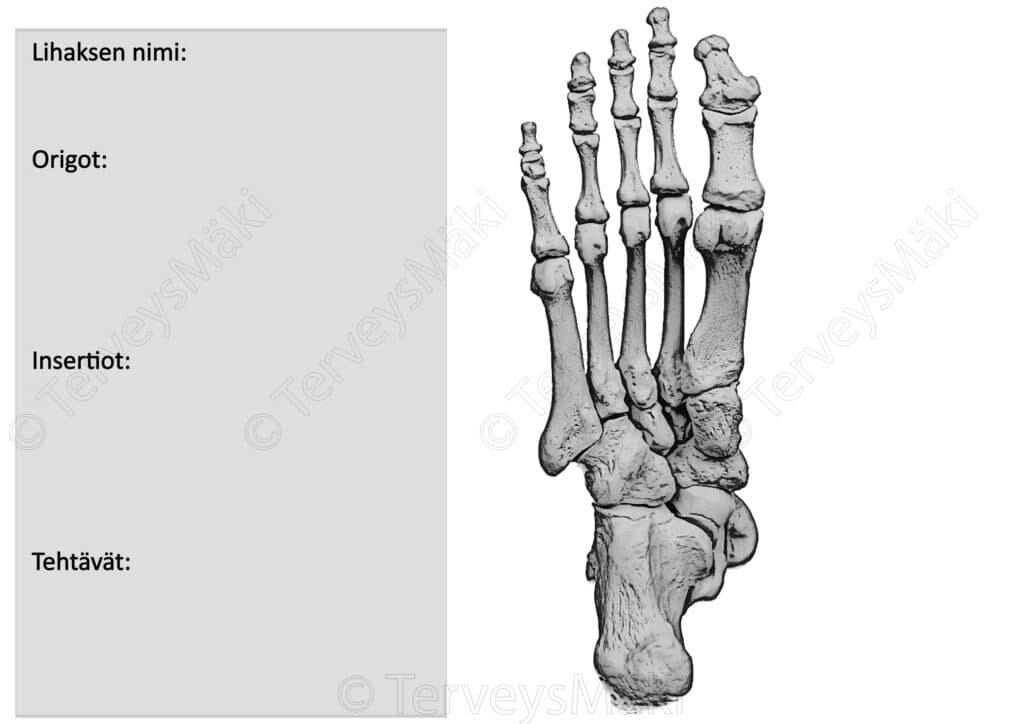

Tehtävä 1:

Voit vapaasti tallentaa ja tulostaa alla olevan kuvan.

- Väritä kuvan luupohjaan lihaksen lähtö- ja kiinnityskohdat.

- Piirrä kyseessä olevan lihaksen lihasrunko.

- Kirjoita oheiseen pohjaan:

- Lihaksen nimi suomeksi ja latinaksi.

- Lihaksen lähtö- ja kiinnityskohdat suomeksi ja latinaksi.

- Lihaksen tehtävät.